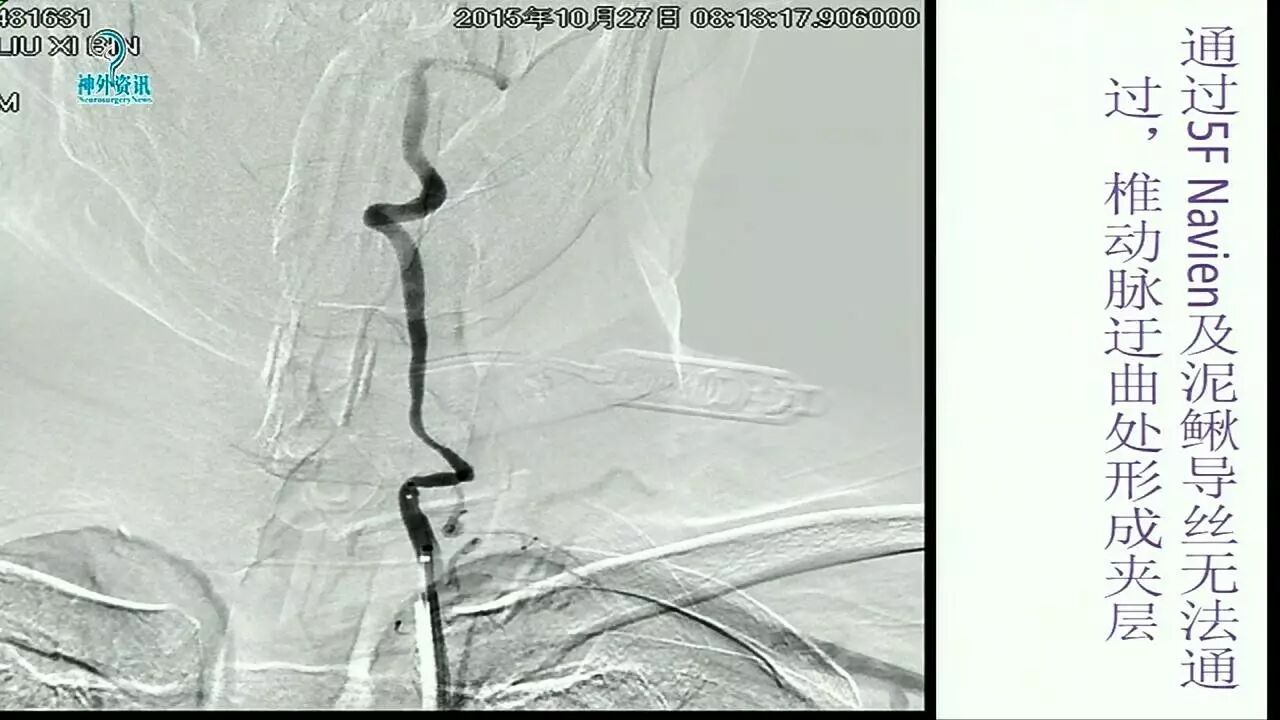

Enterprise支架在缺血性脑血管病中的应用